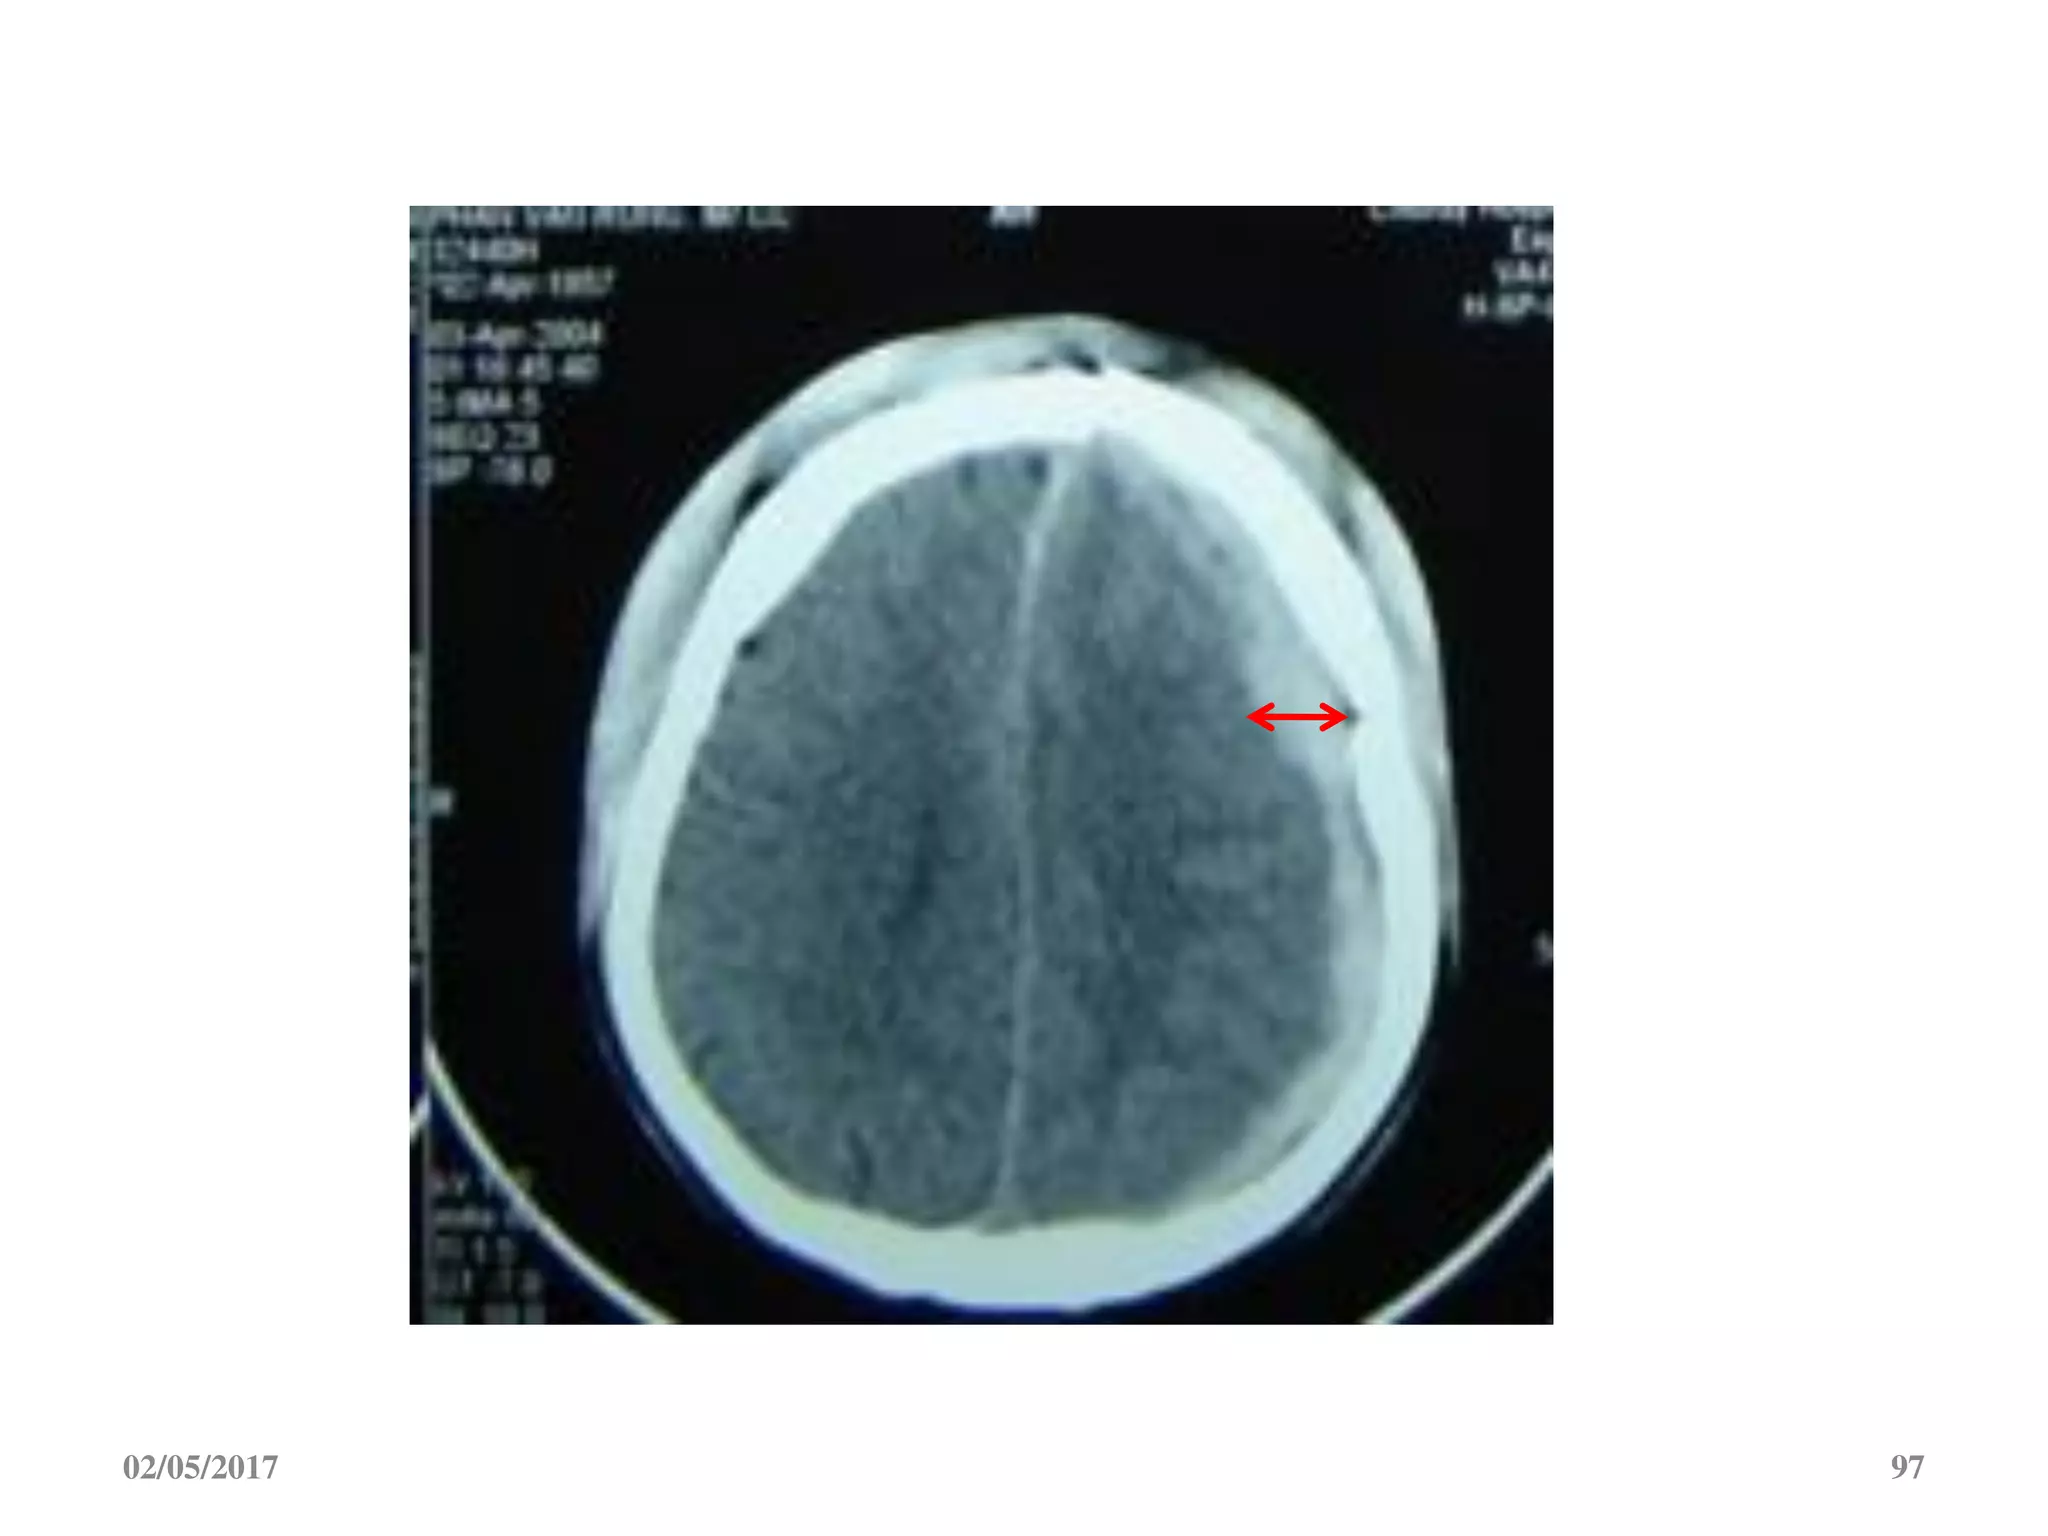

Máu tụ dưới màng cứng cấp

 Ngoài trục, hình liềm,

tăng đậm độ

 Vượt qua được các

khớp sọ

 Thường kèm dập não

An acute subdural hematoma (SDH) with a

thickness greater than 10 mm or a midline

shift greater than 5 mm on computed

tomographic (CT) scan should be surgically

evacuated, regardless of the patient’s

Glasgow Coma Scale (GCS) score

Neurosurgery 58:S2-16-S2-24, 2006

1. Bề dầy máu tụ >10mm hoặc di lệch đường

giữa >5 mm trên CT, nên mổ bất kể điểm GCS